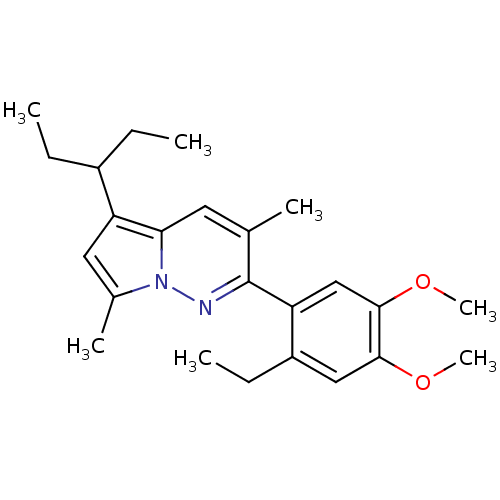

TargetCorticotropin-releasing factor receptor 1(Rattus norvegicus (rat))

Minase Research Institute

Curated by ChEMBL

Minase Research Institute

Curated by ChEMBL

Affinity DataEC50: 2.60nMAssay Description:Antagonist activity at rat CRF1 receptor expressed in CHO-K1 cells assessed as CRF-stimulated cAMP accumulation by enzyme immunoassayMore data for this Ligand-Target Pair